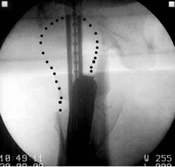

Das Ergebnis ist eine Fehlplazierung der Schenkel- halsschraube Diese korrekte Lage wurde mit dem neuartigen Zielgerät erreicht. Das neue Zielgerät läßt sich leicht auf dem Obturator befestigen und zielt sowohl in der Aufsicht, als auch in der Seitaufnahme. Links ist die falsche Position und rechts durch Drehung des Zielgerätes die korrekte Position zu sehen. Liegen die drei Drähte nun zu weit Proximal, muß der Nagel wieter nach distal geschoben werden.

Position des Gerätes in seitlicher Lage ergibt beim Röntgen die folgenden Aufnahmen. Der geriffelte Draht liegt nicht zwischen den zwei glatten Drähten. Bewegen des Zielgerätes ergibt das erforderliche Bild. Sollten die so positionierten Drähte sich nicht über dem Kopf abbilden, muß der Nagel gedreht werden. Auf diese Weise erreicht man die korrekte Lage der Schenkelhalsschraube in die Mitte des Kopfes, ein Auswandern der Schraube ist so unmöglich.